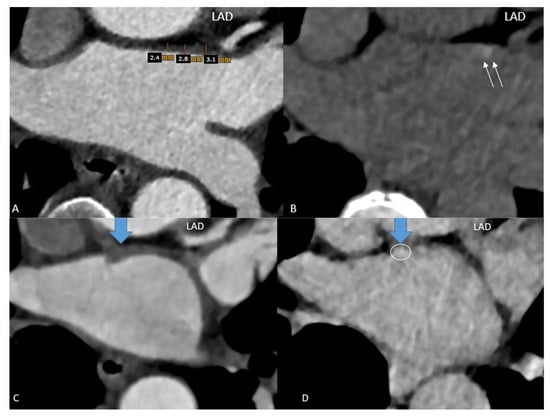

Scan II LE-CT: Axial LE-CT images were co-axially aligned with the CTA datasets on two screens. The left main and proximal left anterior descending (LAD) coronary arteries served as landmarks for co-axial image alignment (Figure 1).

Figure 1. Focal late enhancement (LE). Images (A) of the early phase CTA were co-axially aligned with late enhancement CT performed 7 min after contrast agent injection (B) (2-step CT protocol). (A) LAWT was measured at 3 sites along the LA ridge, and the mean was calculated. The left anterior descending (LAD) coronary artery served as a landmark for co-axial alignment in this patient: a 52-year-old-female with persistent AF, a CVRF of active smoking. The LAWT was >2 mm (A) and focal LE with 130 HU (B) was observed. (C,D) Results in a 54-year-old male with AF prior to planning LA ablation. The mean LAWT was 4 mm (C), and a focal dense spot of late enhancement (LE) was identified at the exact site of maximal LAWT, with 102 HU (D).